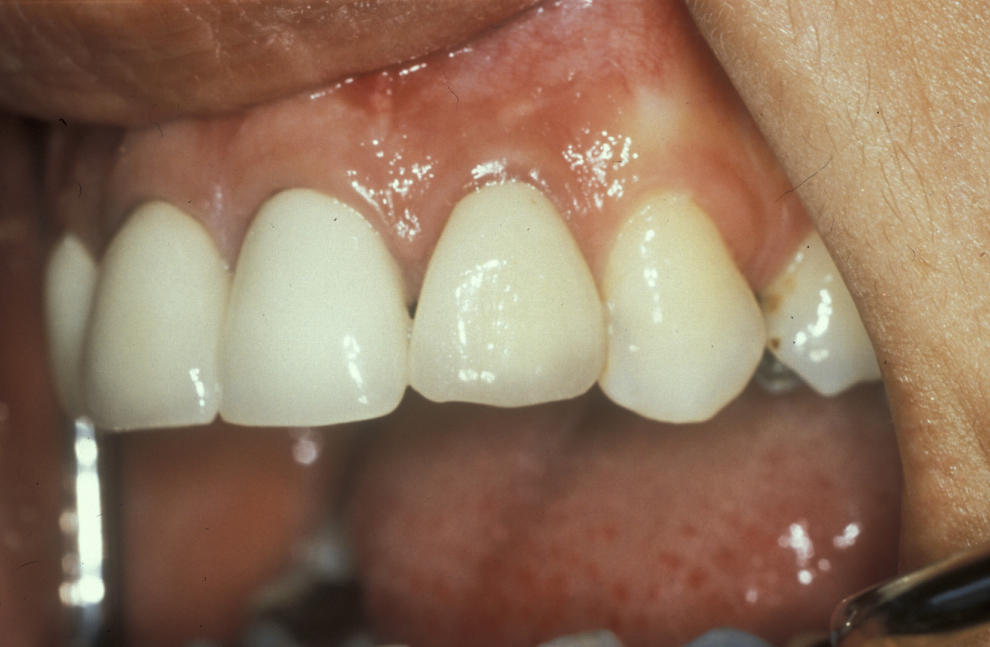

Once endodontic surgery has been performed, it should be assessed after at least one year. Success is indicated by:

- absence of symptoms such as pain and swelling;

- no sinus tract (abnormal draining channel);

- no loss of function;

- satisfactory soft tissue healing;

- X-ray radiographic evidence of bony infill at the surgical site.

Figure 6 depicts the appearance one year after a surgical endodontics intervention. Long-term follow up is based on personal protocol after one year.